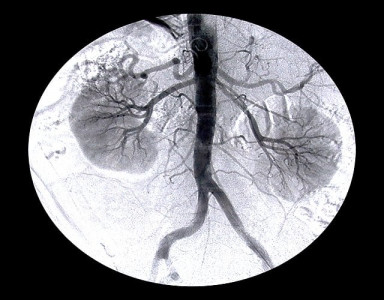

LGH hosts workshop on kidney surgery